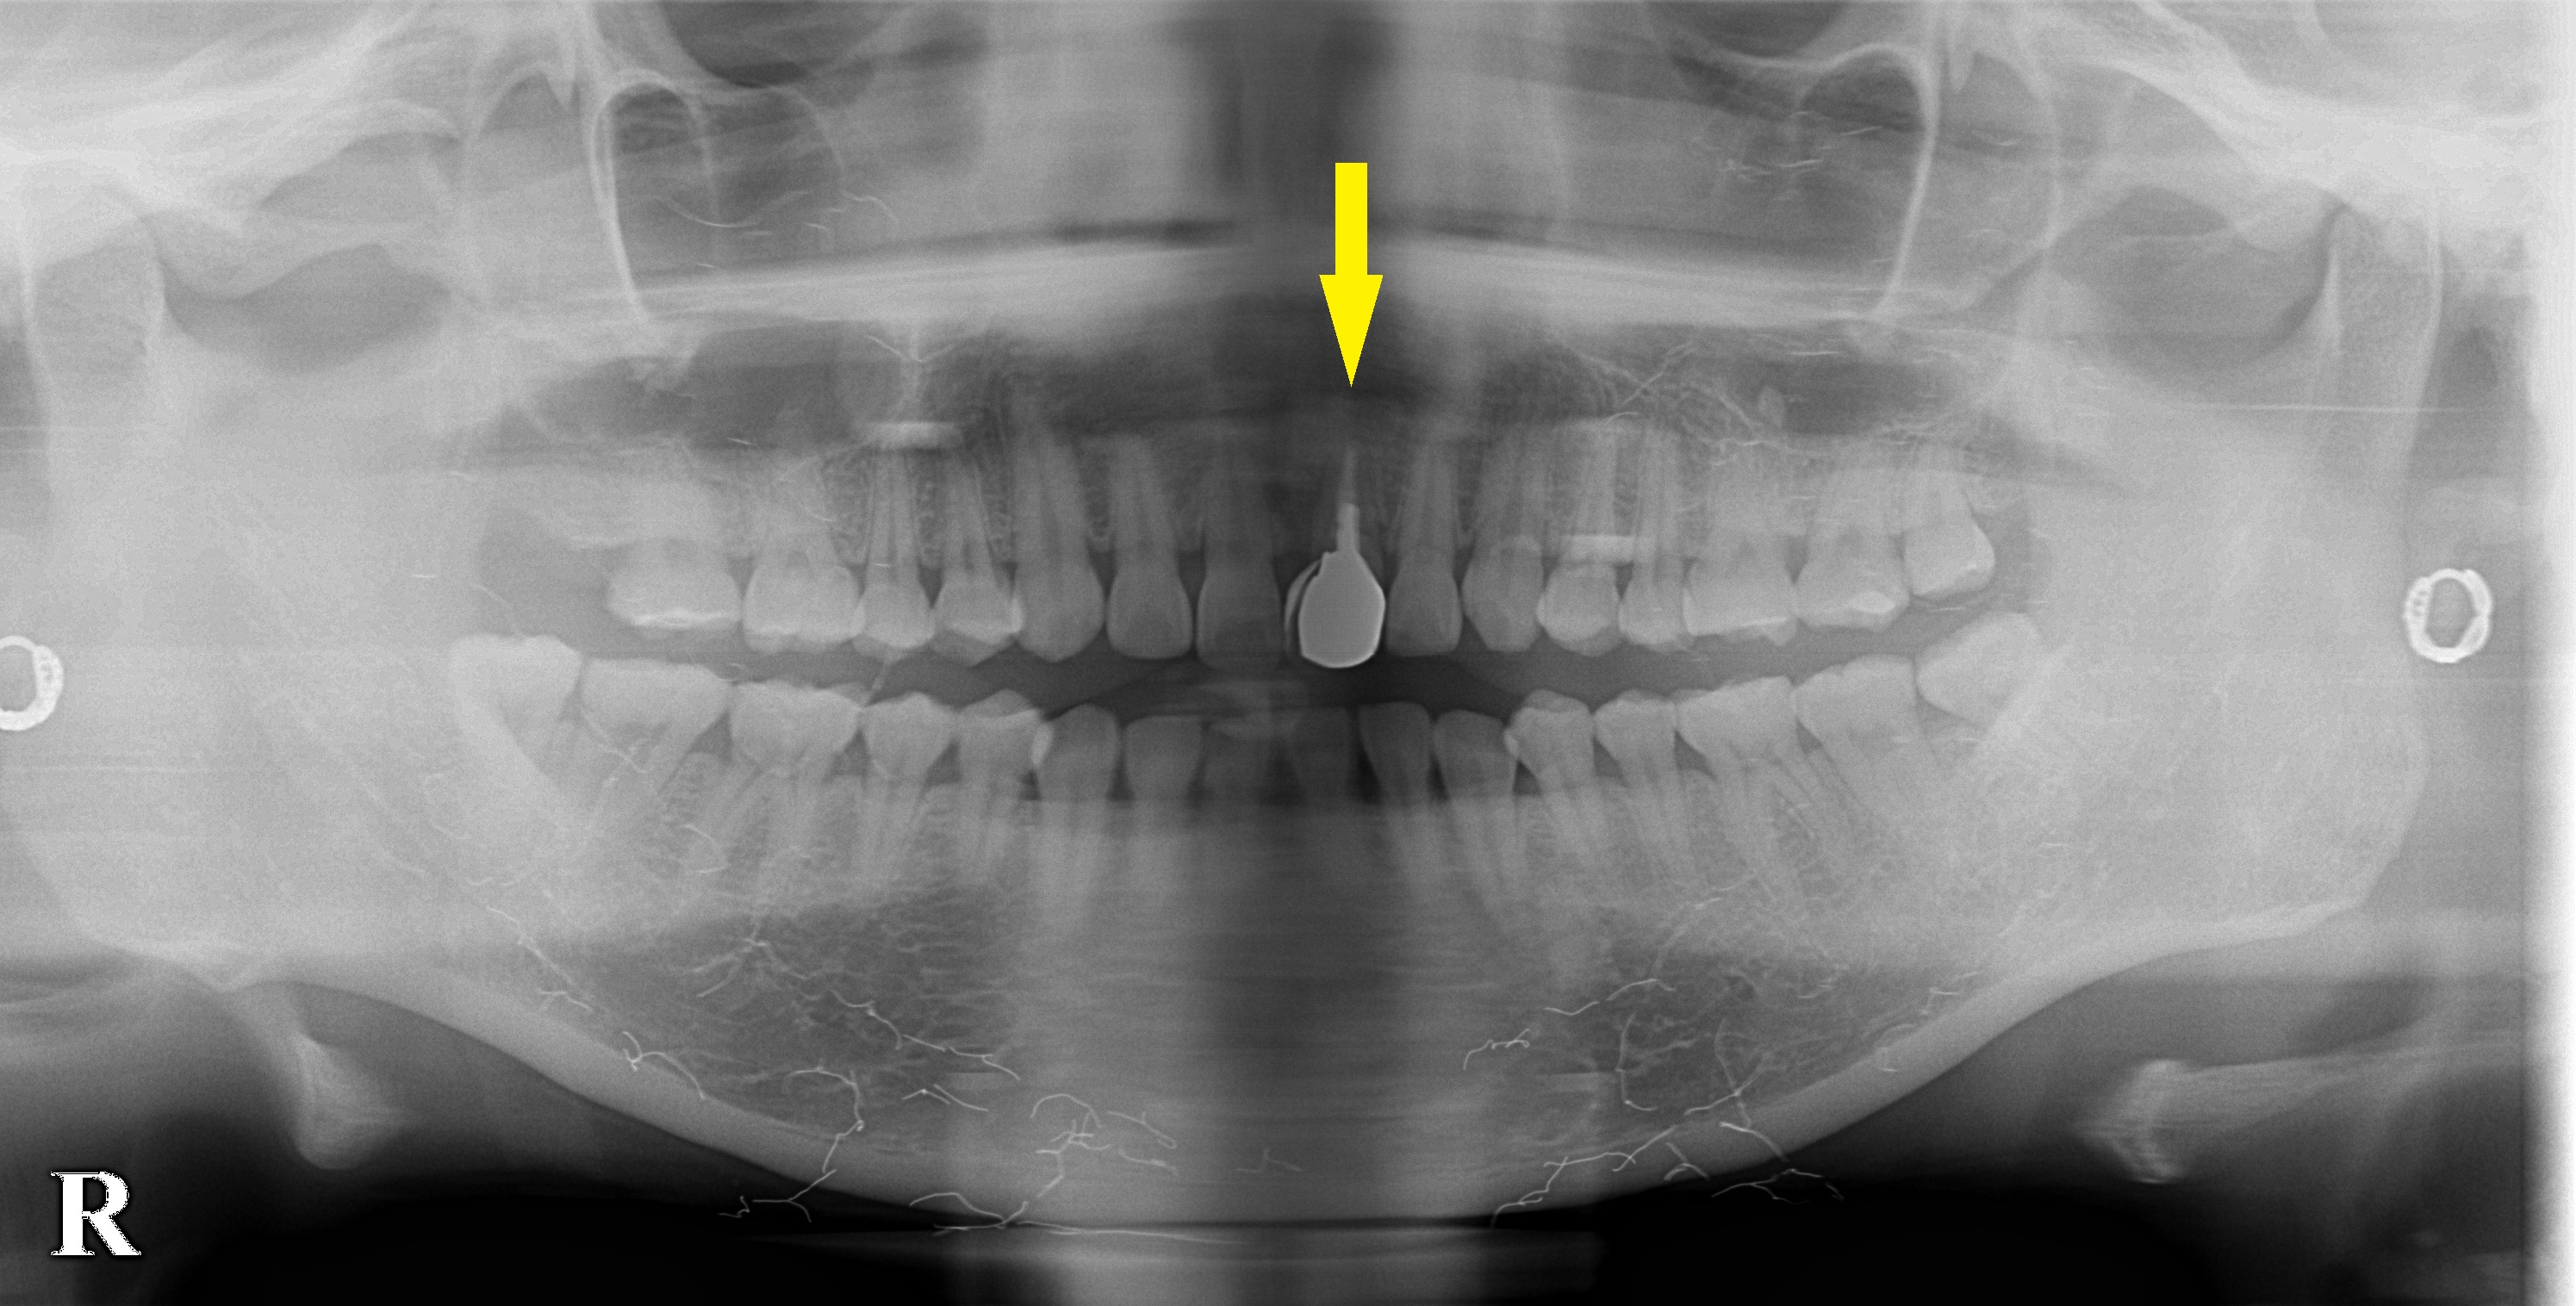

前歯ですので、抜歯して、同時にインプラントを埋入し、さらにそのまま固定式の仮歯を装着する、抜歯即時インプラント埋入、即時修復という方法を提案させていただき、本日、施行しました。

下段左の写真が、抜歯前のCT、下段右の写真が、抜歯した部位にインプラントを埋入したCTです。

黄色矢印部分は、骨とインプラントの隙間に骨補填材を填入した部分で、骨よりもやや白っぽく写っています。